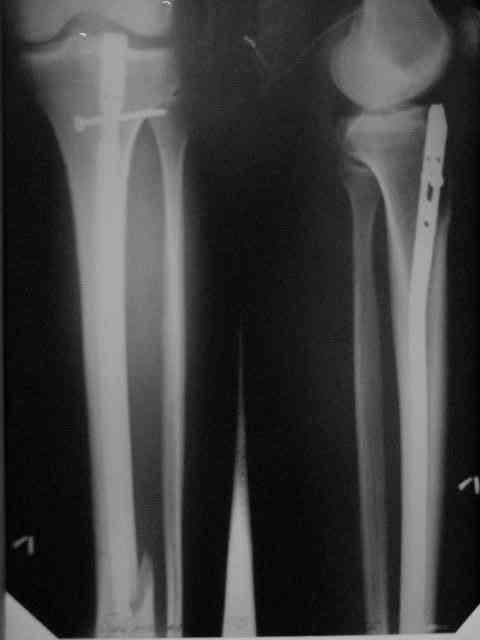

Здравствуйте коллеги!Больной 29 лет поступил 1 мая с Диагнозом: Закрытый спиральный перелом н/3 большеберцовой кости, перелом в/3 малоберцовой.

На пятые сутки выполнен вот такой остеосинтез (см R-gr) . На сегодня мы имеем перелом нижнего винта, замедленное сращение( R- gr от 11.09.06) Больного ничего не беспокоит, ходит с костылями с ограниченной нагрузкой. На наш взгляд возможно обойтись :1 Удаление сломанного винта и верхнего блокирующего с последующим более глубоким погружением штифта и его дистальным блокированием. Либо замена на более длинный (Экперт-Синтез).2 Остеотомия косая малоберцовой кости.С большим вниманием выслушаем возможные варианты, тактики в таком случае.С Уважением Владимир Бахарев.P.S Извинямси за качество снимков!